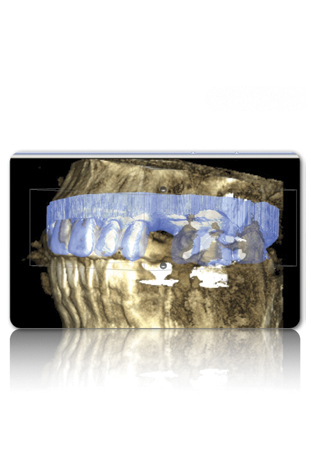

Figure 1 Traditional intraoral bitewing showing limited field of view (Fig 1) compared to the expanded view possible using CBCT (Fig 2).

Figure 1

Figure 2 Traditional intraoral bitewing showing limited field of view (Fig 1) compared to the expanded view possible using CBCT (Fig 2).

Figure 2

CBCT can also be used in this same manner to perform an even more common task, bitewing images, which are clinically indicated as often as every 18 to 24 months. For hygiene patients whose films require updating, CBCT offers a “patient-friendly” approach. Given that these films, which are usually performed intraorally, are often taken on an hourly basis in the typical general practice, the technology can be well utilized while also increasing comfort and satisfaction among patients. In addition, due to the expanded field of view that can be achieved with these extraoral CBCT images, they can often be more diagnostically valuable than images produced with an intraoral sensor (Figure 1 and Figure 2).